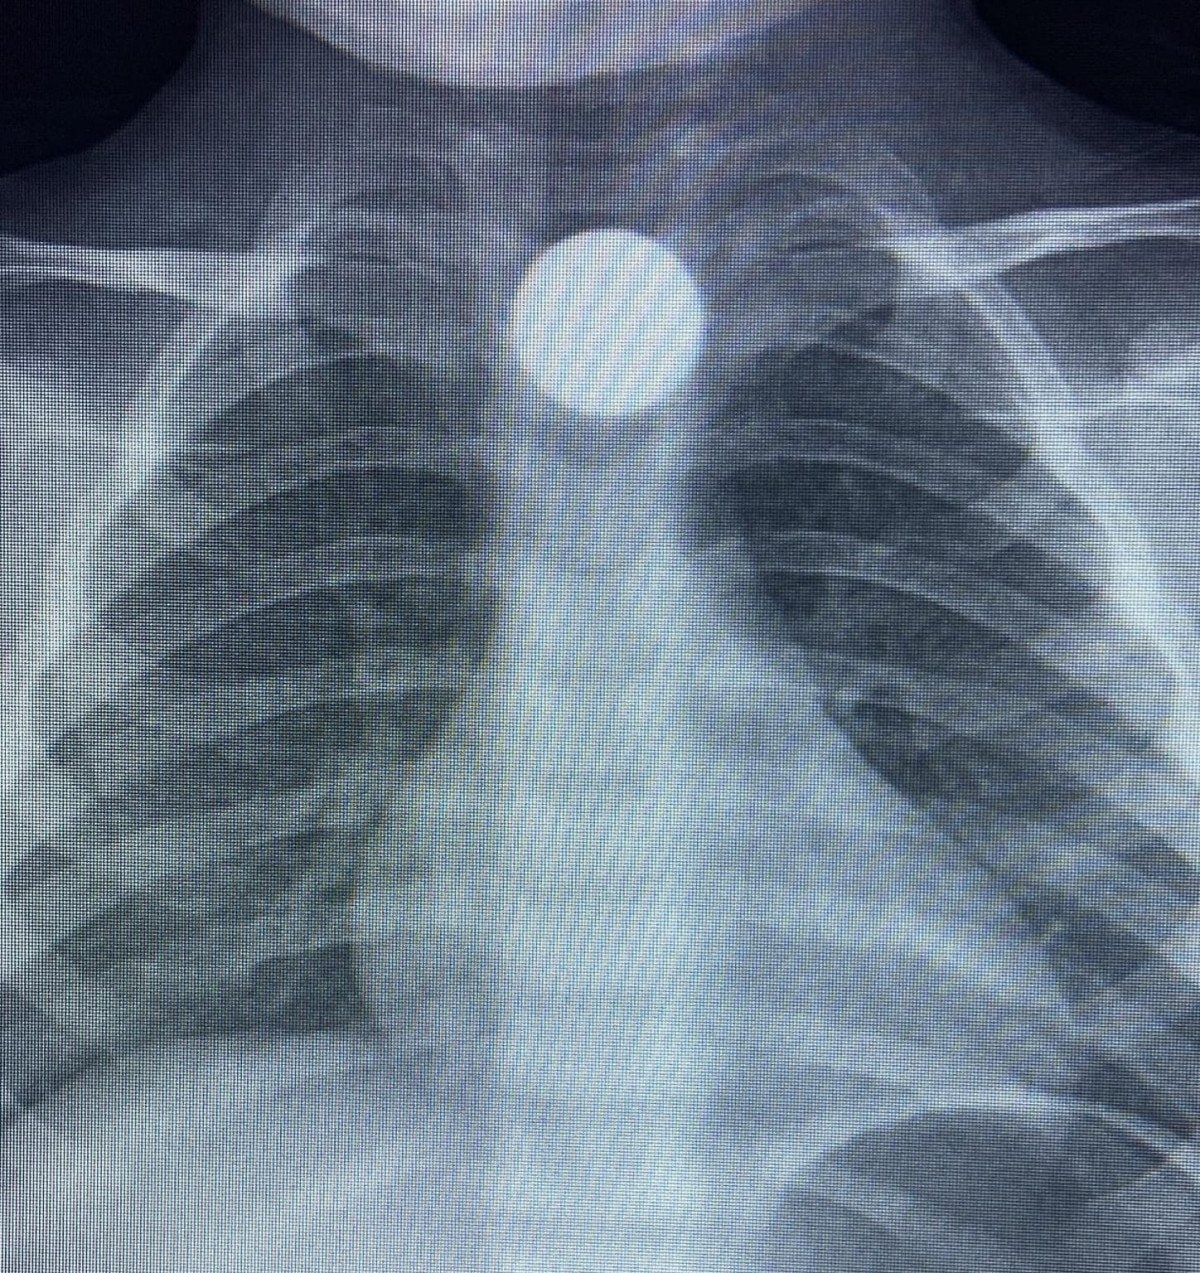

Çocuğun parayı yuttuğunu fark eden ailesi, Bilal K.’yi vakit kaybetmeden özel araçla İnegöl Devlet Hastanesi’ne götürdü. Hastanede yapılan muayene ve görüntüleme işlemlerinde, madeni paranın çocuğun yemek borusunda takılı kaldığı tespit edildi.

İlk müdahalesi İnegöl Devlet Hastanesi’nde yapılan Bilal K., ileri tetkik ve tedavi amacıyla ambulansla Bursa Yüksek İhtisas Eğitim ve Araştırma Hastanesi’ne sevk edildi.